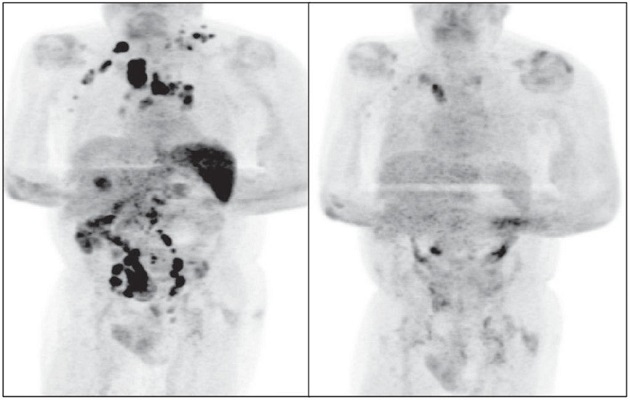

Cuatro meses después, la inflamación de los ganglios se había reducido y una exploración PET reveló una remisión generalizada del linfoma.

De acuerdo con los autores de la publicación, que detalla The Conversation y la BBC, la hipótesis es que la  infección por SARS-CoV-2 desencadenó una respuesta inmunitaria antitumoral: las citocinas inflamatorias producidas en respuesta a la infección podrían haber activado células T específicas con antígenos tumorales y células asesinas naturales contra el tumor. El SARS-CoV-2 le habría curado el linfoma.